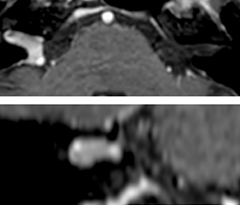

Giant cell arteritis

The 3D TSE T1w black blood MSDE sequence with fat suppression has an isotropic 0.8 mm voxel size and sagittal oblique and axial reformats are made. The images show superficial temporal artery thickening and peri-arterial fat infiltration. The 3D TSE PDw black blood MSDE with fat suppression has 0.55 mm isotropic voxels. The images shows focal involvement of the frontal branch of the superficial temporal artery.

3D TSE T1w BB MSDE

3D TSE PDw BB MSDE